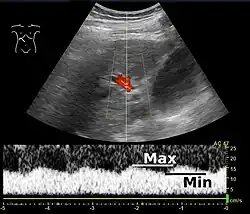

Increased blood pressure in the portal vein, called portal hypertension, is a major complication of liver disease, most commonly cirrhosis.[7] A dilated portal vein (diameter of greater than 13 or 15 mm) is a sign of portal hypertension, with a sensitivity estimated at 12.5% or 40%.[8] On Doppler ultrasonography, the main portal vein (MPV) peak systolic velocity normally ranges between 20 cm/s and 40 cm/s.[9] A slow velocity of <16 cm/s in addition to dilatation in the MPV are diagnostic of portal hypertension.[9]

Portal vein pulsatility can be measured by Doppler ultrasonography. An increased pulsatility may be caused by cirrhosis, as well as increased right atrial pressure (which in turn may be caused by right heart failure or tricuspid regurgitation).[9] Portal vein pulsatility can be quantified by pulsatility indices (PI), where an index above a certain cutoff indicates pathology:

| Average-based | (Max - Min) / Average[9] | 0.5[9] |

| Max-based | (Max - Min) / Max[11] | 0.5[11][12] - 0.54[12] |